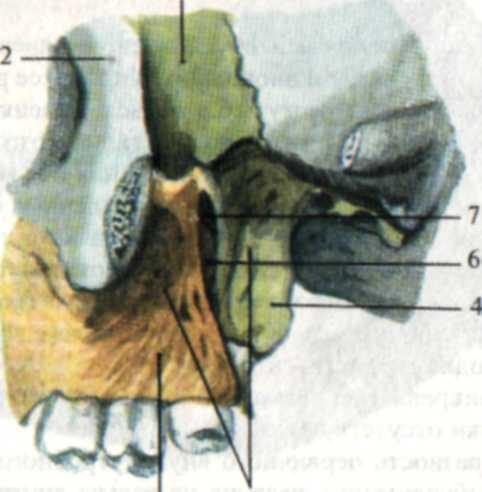

Анатомические особенности: фотографии ямок черепа, височной и подвисочной крылонебной